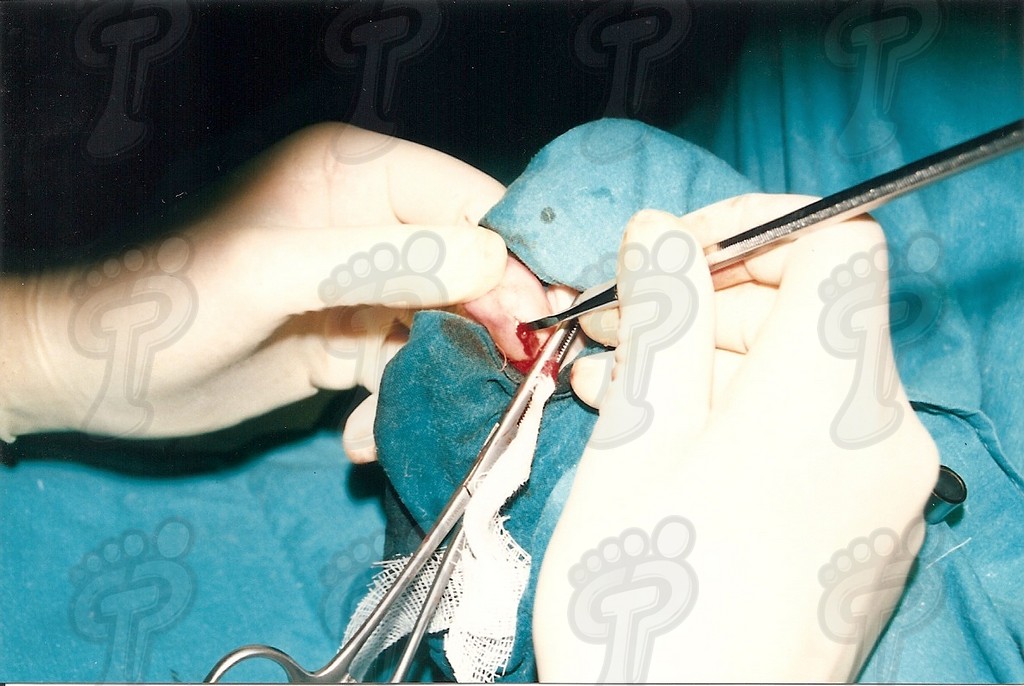

Se realiza la técnica mediante anestesia troncular y sin hemostasia (o al menos, tras el legrado). Hacemos una incisión transversal en la zona dorsoplantar distal a dos o tres milímetros de la prominencia ósea, se introduce el bisturí perpendicularmente al eje de la falange hasta tocar hueso, y a partir de ahí, se desciende bien próximo al tejido ósea para separar partes blandas y delimitar la exóstosis. No se debe incidir lateralmente porque podríamos dañar el paquete neurovascular. Se introduce un cincel separando tejido óseo blando y se delimita la prominencia ósea, la cual suele ser mayor que en la radiografía debido a una zona cartilaginosa radiotransparente. Se legra exhaustivamente con la lima de proximal a distal y de profundidad a superficie (sin vaivén). En las primeras capas (cortical y periostio) notamos que la lima patina y a continuación percibimos el raspado óseo. Con el pulgar de la mano pasiva presionamos de proximal a distal para que salgan al exterior las partículas óseas legradas. Legramos ampliamente ya que al producir un traumatismo óseo siempre hay una regeneración ósea debida a la rica red capilar superficial. Si no lo hacemos así, se puede volver a regenerar el tejido óseo produciendo de nuevo y en poco tiempo la exóstosis. Favorecemos el sangrado de la zona para ayudar a eliminar posibles partículas óseas. Lavamos abundantemente la incisión con suero fisiológico. Volvemos a realizar otra radiografía dorsoplantar intraquirúrgica, a ser posible en la misma posición pre-quirúrgica (la radiografía oblícua no da imagen real del tamaño de exóstosis y la lateral no muestra nada). Hemos de observar en la radiografía que la cabeza de la falange proximal está en el mismo plano que la base de la falange media, ya que si no puede producir algias post-operatorias. Si observamos una nebulosa en la radiografía, son pequeñas partículas o fragmentos óseos que deben drenarse mediante lavados ya que si no se reagrupan y vuelven a regenerar la exóstosis de nuevo. Se han de hacer lavados y radiografías hasta quedar la zona totalmente limpia de fragmentos óseos. Infiltramos anestésico y corticoides en proporción 9 a 1. No hemos de abusar del corticoide porque al entrar en contacto con la trabécula ósea que hemos dejado como capa externa, puede producir problemas graves post-operatorios, tales como la osteoporosis. Se aconseja primero cargar el corticoide y luego el anestésico para evitar que se cristalice el corticoide produciendo trastornos yatrogénicos. Una vez infiltrada la mezcla, presionamos la herida proximal a distal para drenarla ya que sólo nos interesa el efecto farmacológico antiinflamatorio. A continuación, suturamos con seda 5/0 mediante dos puntos simples. En el caso que os mostramos ferulizamos el quinto dedo con una gasa de “U”, impidiendo así la movilización dorsoplantar y, para más sujeción, se une al cuarto dedo con la ayuda de un vendaje circular. Puede impregnarse en yodo la férula en forma de “U” para darle mayor rigidez o consistencia y por lo tanto, menor movilidad al quinto dedo. El vendaje debe ser semicompresivo alineado el dedo. Aconsejamos al paciente reposo durante 48 horas. Pautamos la analgesia correspondiente, y le informamos de las actuaciones que debe efectuar ante determinadas anomalías. Retiramos el apósito quirúrgico a las 48 horas y se cura con povidona yodada dos veces al día (mañana y tarde). Enseñamos al paciente a hacer el vendaje en forma de “U”. A los siete días retiramos la sutura y confeccionamos una cresta de silicona, que debería emplear hasta alcanzar la normalidad articular. Dicha silicona ha de ser utilizada durante un período que oscile entre seis meses a un año.